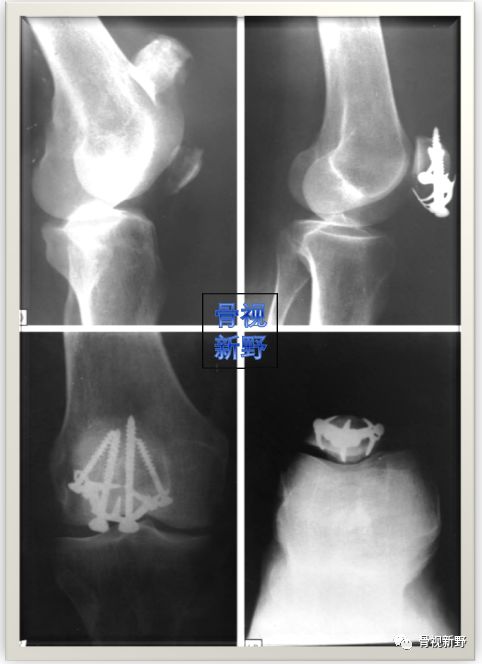

术中所见

X光所见